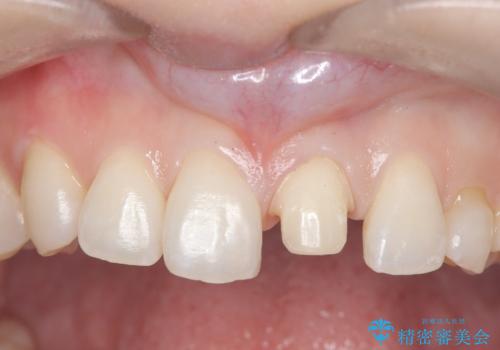

- 以前に前歯を折れた時、コンポジットレジンで修復したが、変色してきたことを主訴に来院されました。

今回は、セラミッククラウンによる修復を希望され、治療を行っています。

コンポジットレジンは、経年変化しやすい材料ですが、セラミックは変色しずらい材料となります。